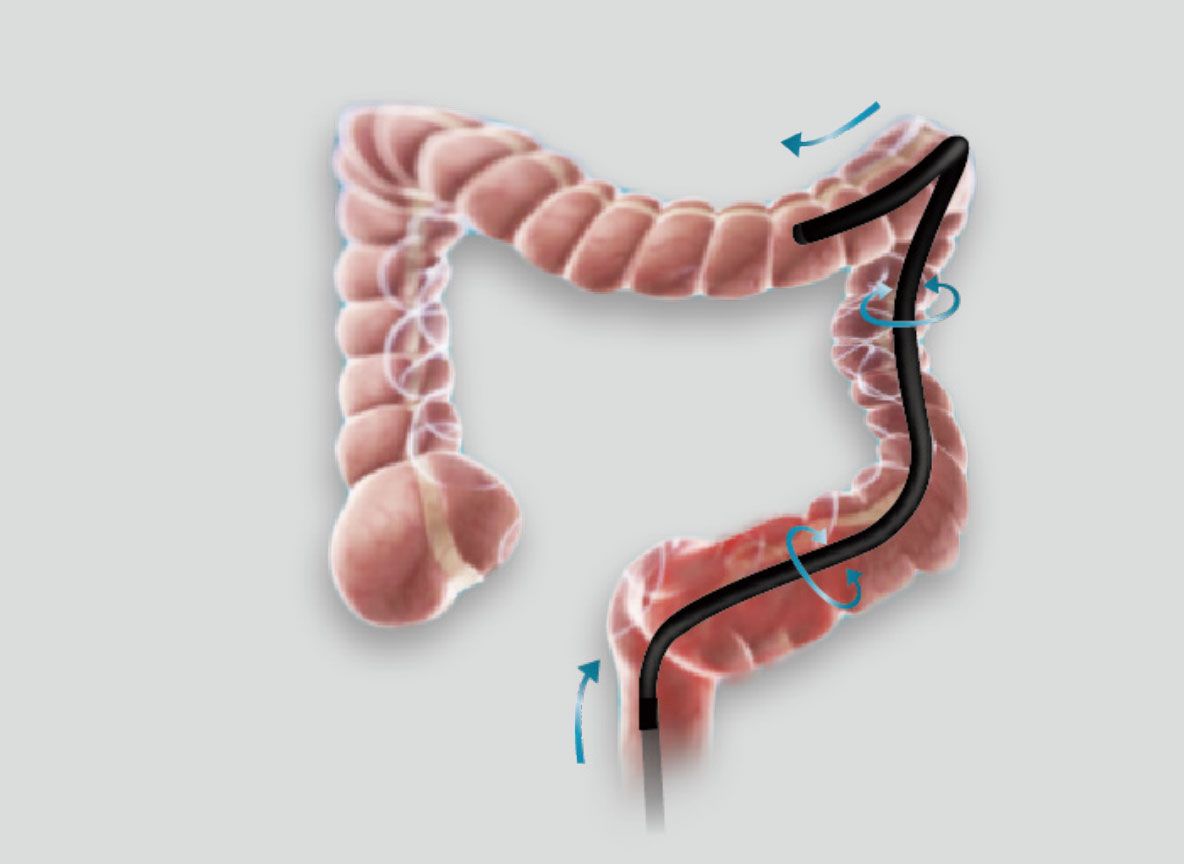

弯曲角度大,方便观察食管下段贲门、胃底部等难以观察到的部位,减少盲区。

带来镜体插入及诊疗新体验。

操作部轻量化设计,按钮布局合理,操作便捷。